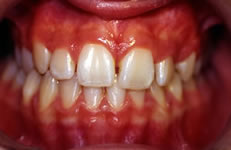

Terapia ortodontica - Prima (FIG 2)

La paziente S.A., di anni 12, presenta morso crociato posteriore monolaterale (fig. 1) dovuto a deviazione della mandibola verso destra in fase chiusura , pertanto le linee interincisive risultano non coincidenti (fig. 2). Si rileva inoltre l’assenza in arcata del canino superiore di sinistra ( incluso) e carenza di spazio per lo stesso (fig. 3 e 4).